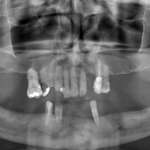

Chirurgia guidata: riabilitazione implanto protesica di agenesia degli incisivi laterali superiori

In questo case report, realizzato dal Dott. Fabio Scarano Catanzaro, viene descritto un intervento di riabilitazione implantare effettuato con pianificazione digitale e chirurgia guidata su...